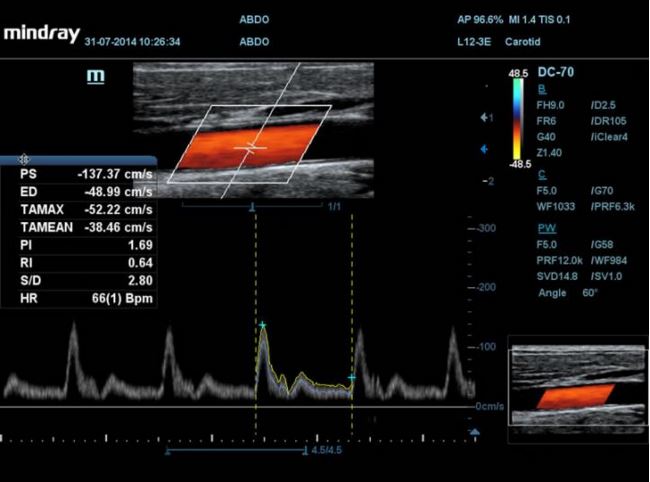

Radiologia

• HR Flow 2-giej generacji /Przepływy o wysokiej rozdzielczości pozwalające uzyskać niezwykłą rozdzielczość przestrzenną.

Zakres aplikacji z pakietami automatycznych pomiarów obejmuje Smart OB, Smart NT, Smart-V, Auto IMT, Auto LV i automatyczny obrys i zliczanie PW,